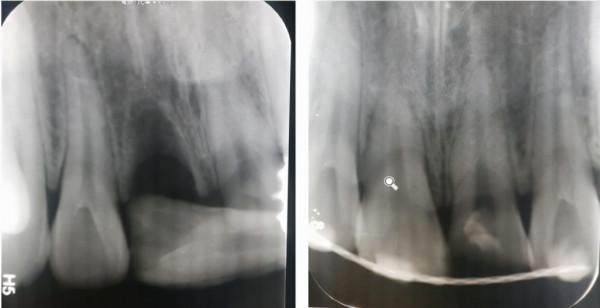

根折--根頸1/3

治療方案:復位鬆動移位的牙冠,夾板固定4周,折斷線近牙頸部固定時間延至4個月,定期檢測折斷線癒合情況,監測牙髓狀態。牙髓壞死或感染則進行冠方的牙髓治療。如頸部折斷後斷片異常鬆動,治療則同冠根折。

根折--根中1/3

治療方案:復位鬆動移位的牙冠,夾板固定4周,定期檢測折斷線癒合情況,監測牙髓狀態。牙髓壞死或感染則進行冠方的牙髓治療。